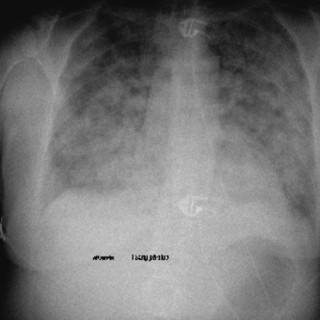

Educational case report